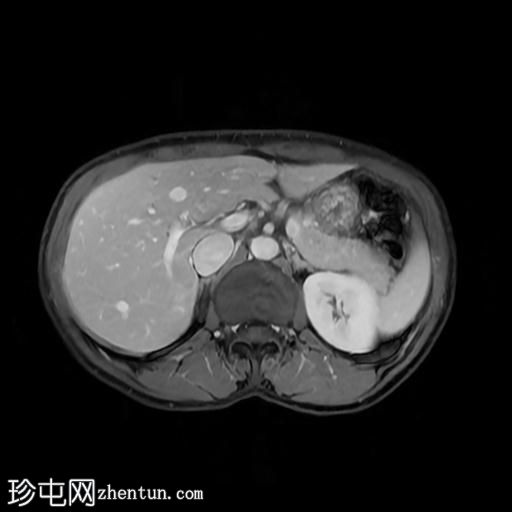

轴位

T1加权像

此外,肝脏第二段左叶可见一 10 x 12 mm 的肝脏肿块,在重 T2 加权像上呈高信号。该病灶呈周边结节状强化,提示为血管瘤。肝脏第八段右叶可见一类似病灶,大小约 10 mm。

此外,右肾中极可见一大小约 5 mm 的肾皮质囊肿。